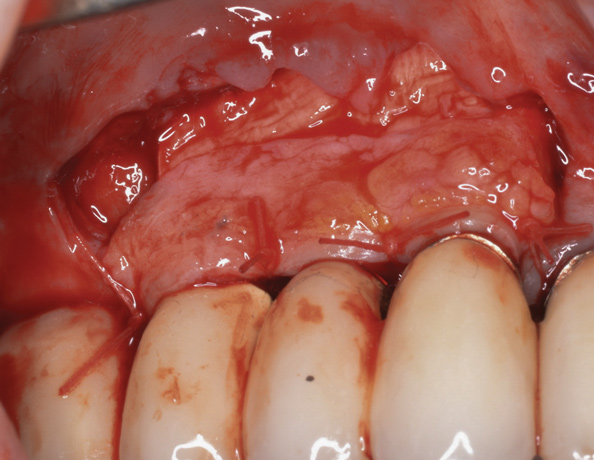

(18.) A subepithelial, connective tissue graft from the palate is affixed over the collagen bone scaffold and around the abutments of the three involved implants.

Figure 18